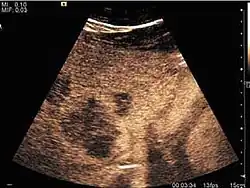

Encephaloid hepatocellular carcinoma (CEUS). Contrast tumor enhancement is observed on the left during arterial phase. The “wash-out” phenomenon can be seen on the right, during portal venous phase.

HCC appearance on 2D ultrasound is that of a solid tumor, with imprecise delineation, with heterogeneous structure, uni- or multilocular (encephaloid form). An "infiltrative" type is also described which is difficult to discriminate from liver nodular reconstruction in cirrhosis. Typically HCC invades liver vessels, primarily the portal veins but also the hepatic veins . Doppler examination detects a high speed arterial flow and low impedance index (correlated with described changes in tumor angiogenesis). The spatial distribution of the vessels is irregular, disordered. CEUS examination shows hyperenhancement of the lesion during the arterial phase. During the portal venous phase there is a specific "wash out" of ultrasound contrast agent (UCA) and the tumor appears hypoechoic during the late phase. Poorly differentiated tumors may have a stronger wash out leading to an isoechoic appearance to the liver parenchyma during portal venous phase. This appearance was found in approx. 30% of cases. The described changes have diagnostic value in liver nodules larger than 2 cm.